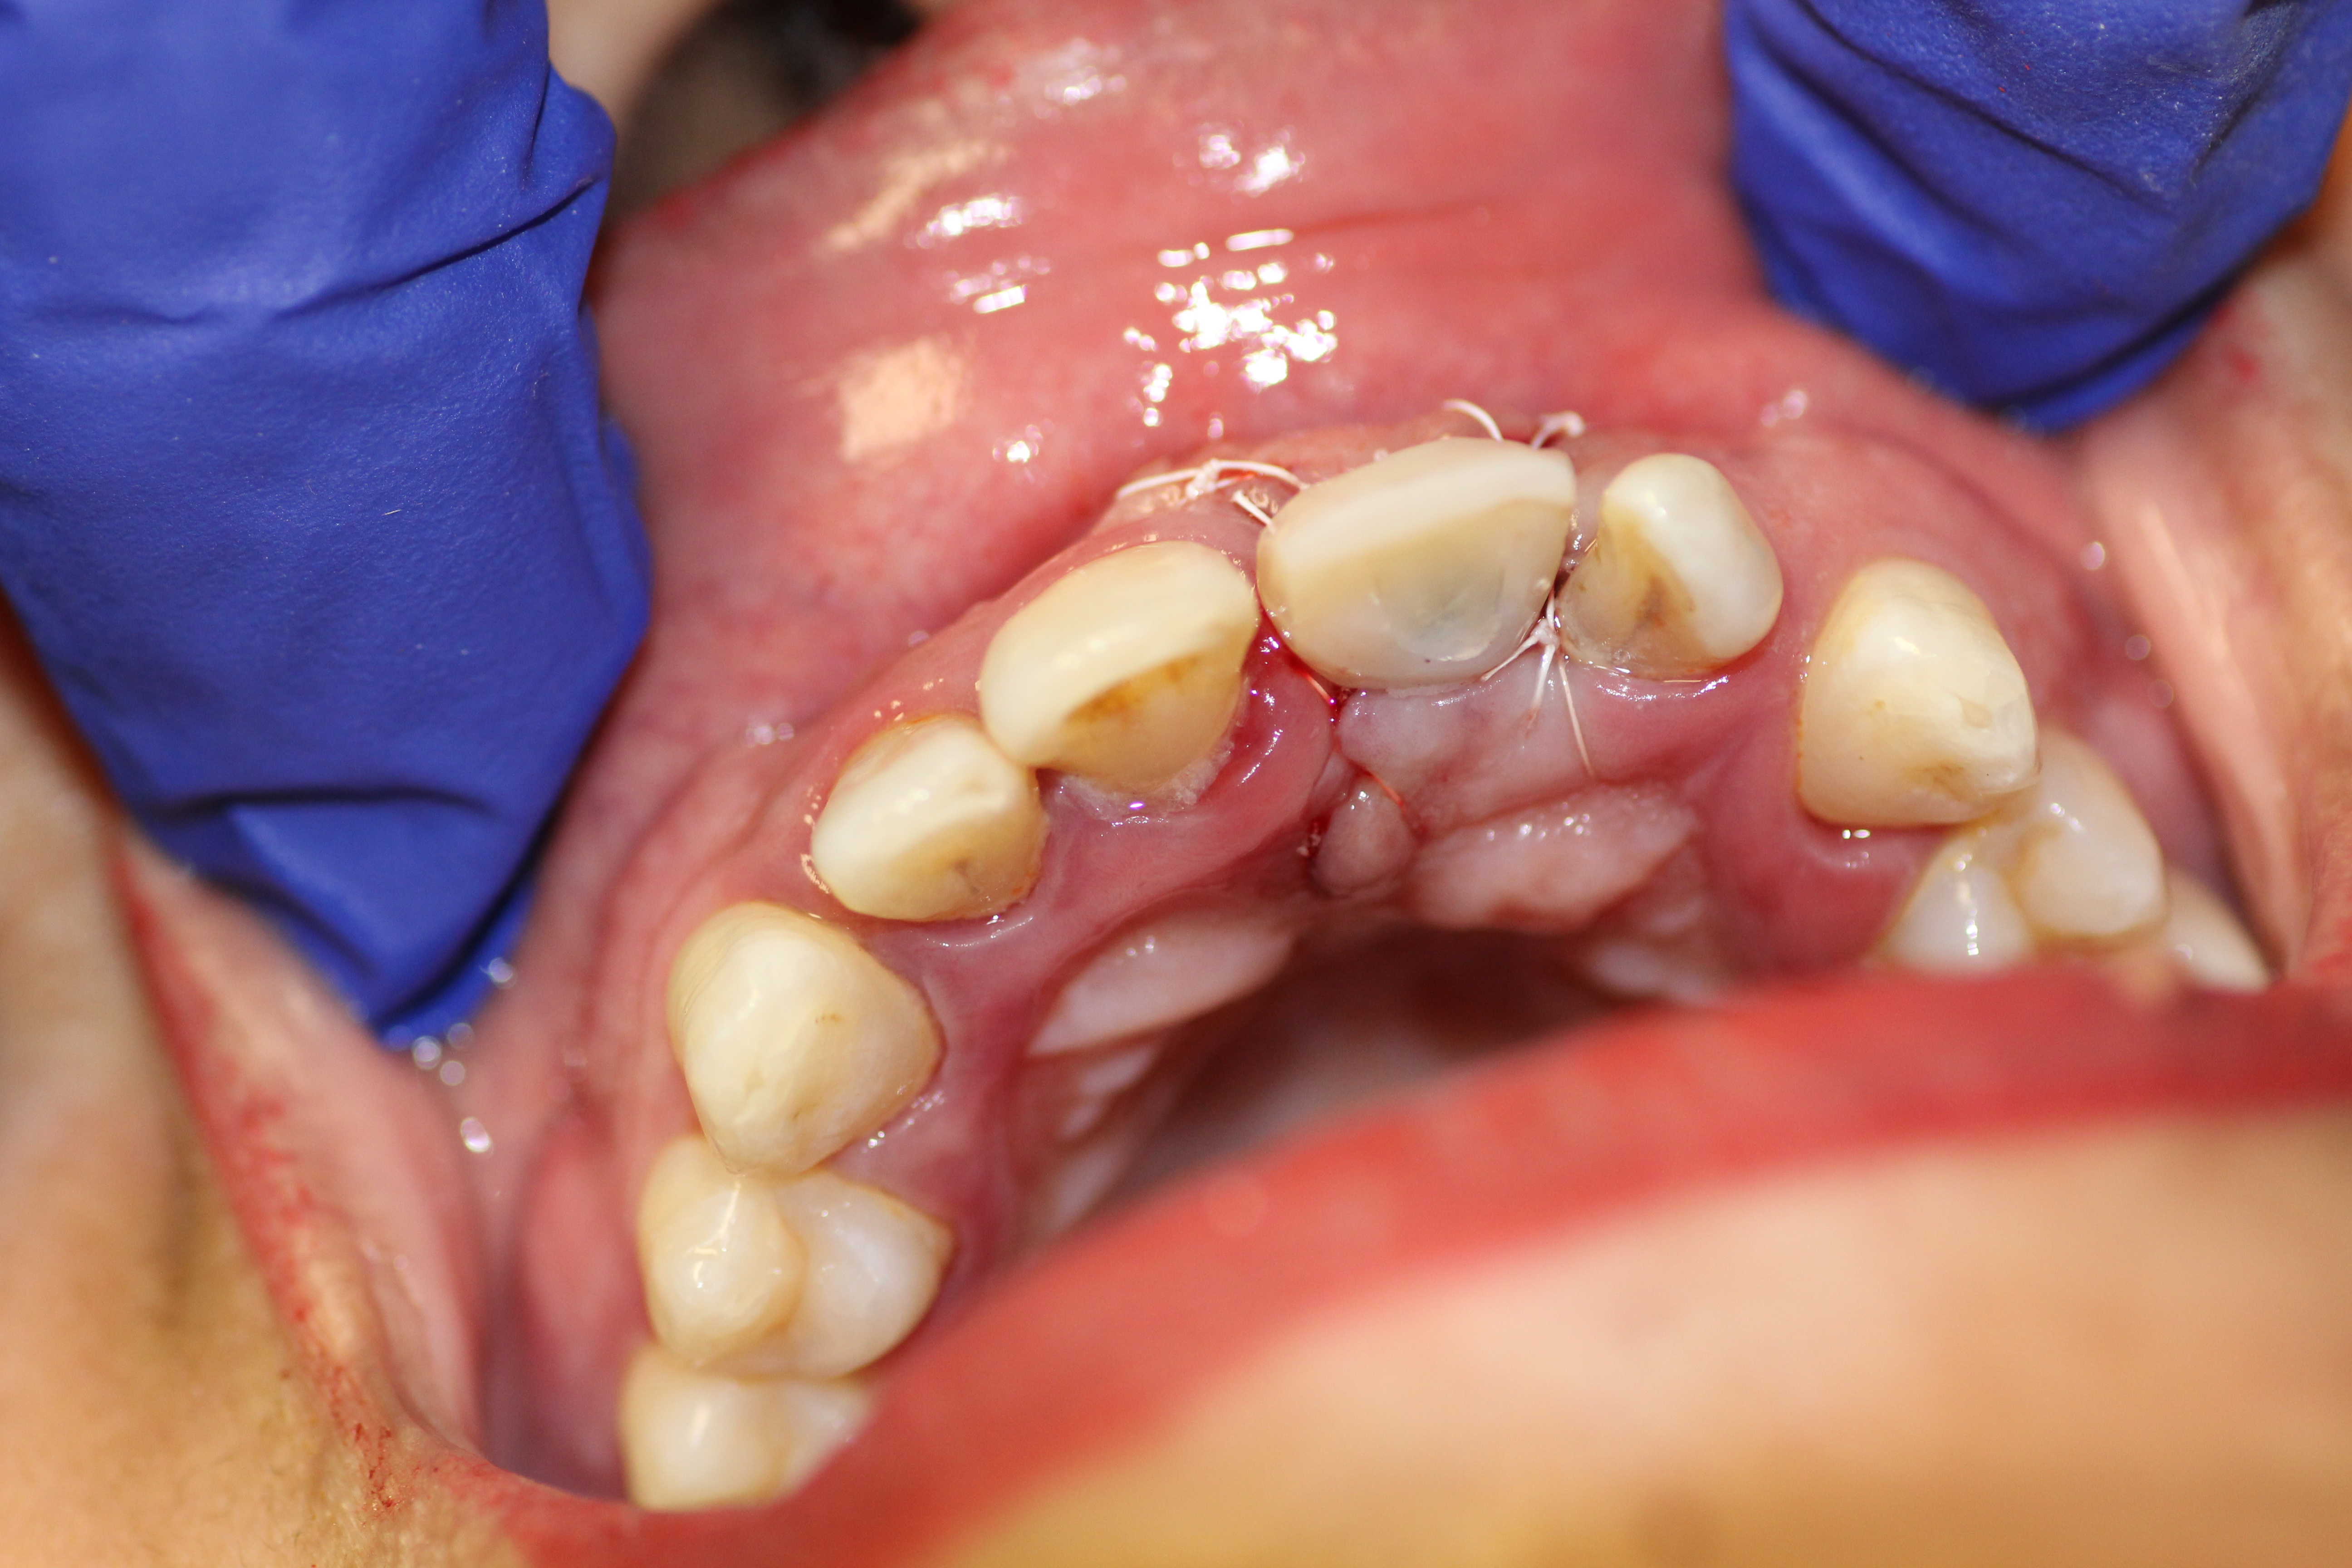

- Implant being sutured while the temporary crown is being made.

-

- Temporary crown made.